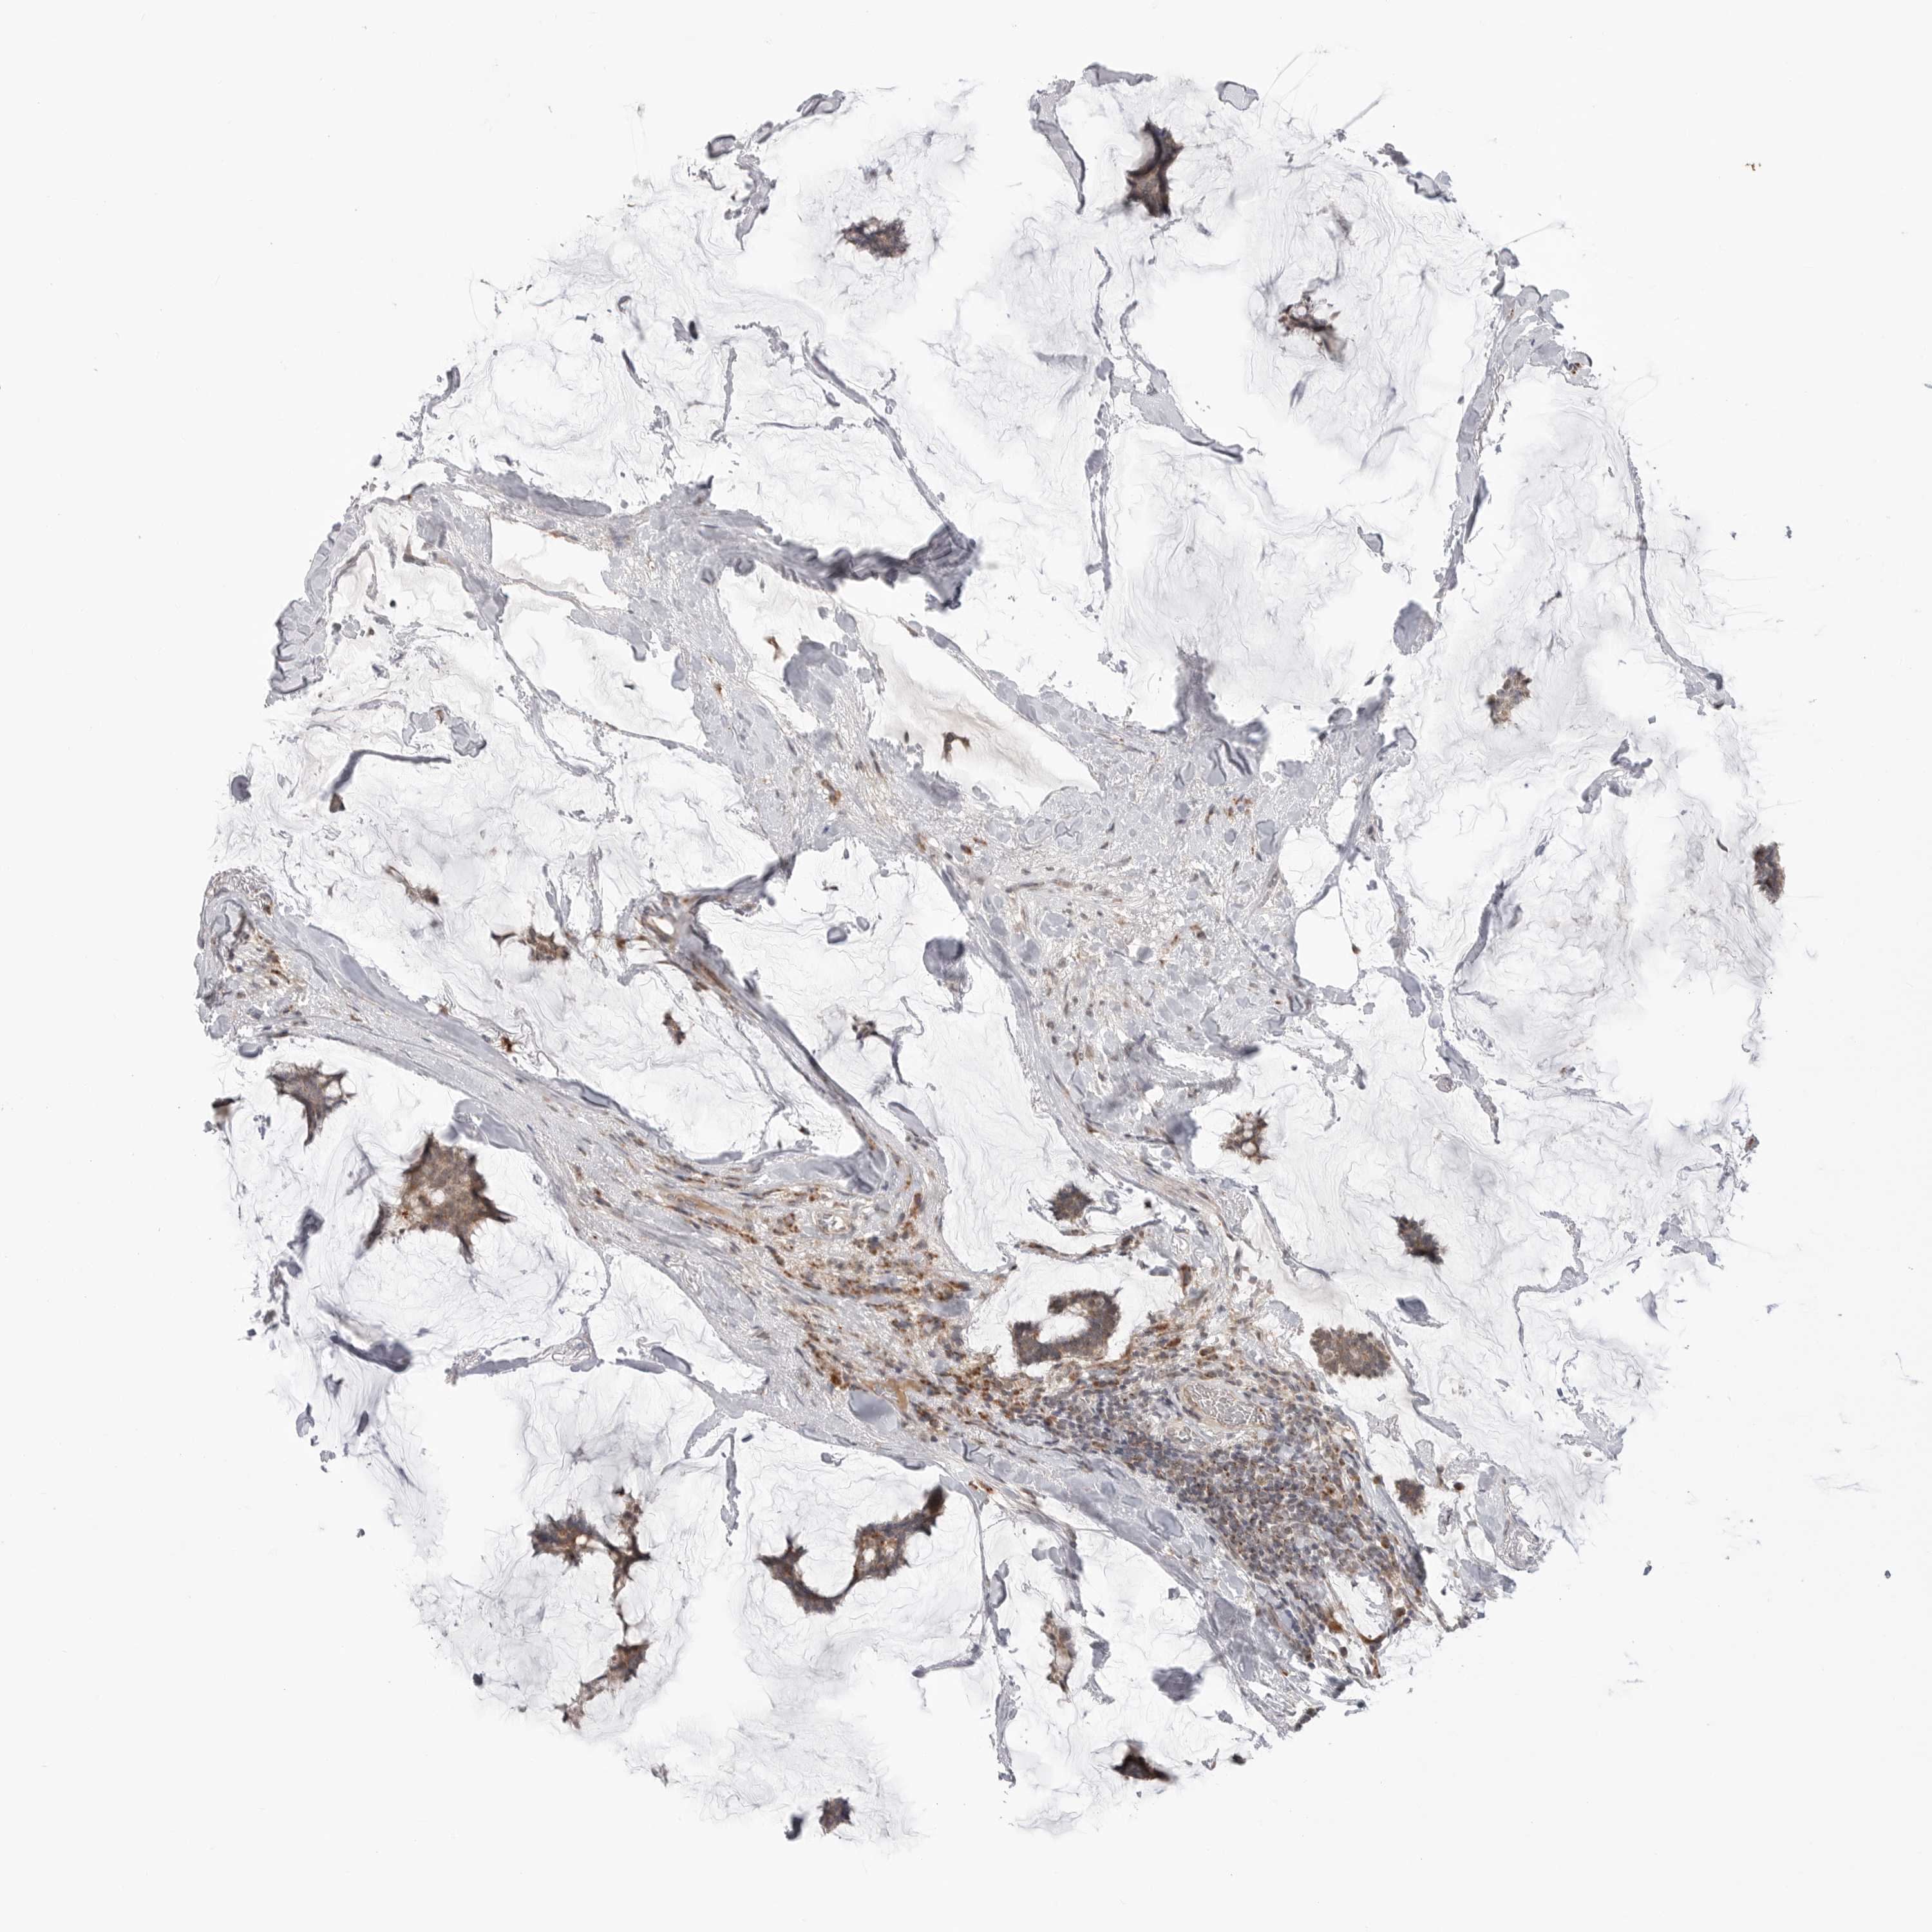

BRCA TCGA BRCA VALIDATION PROTEIN EXPRESSION